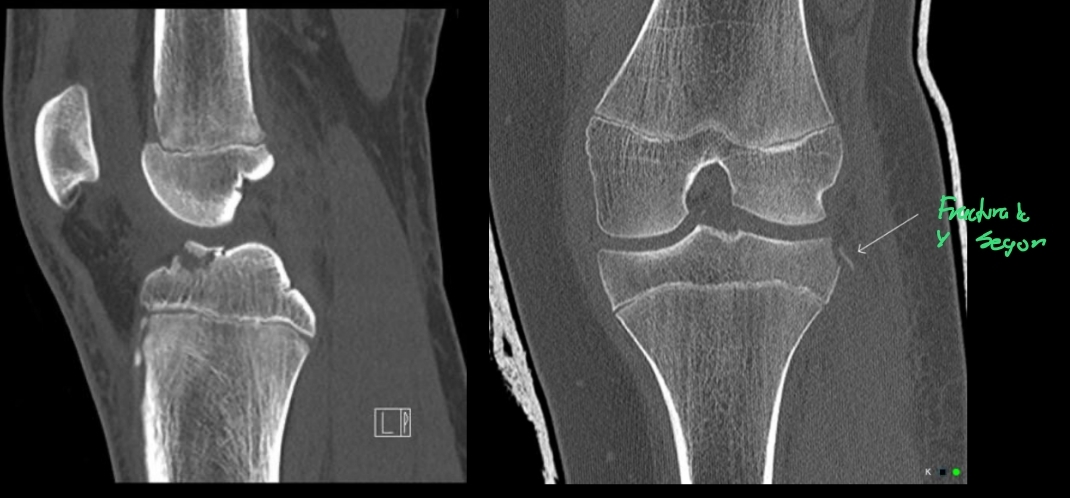

15

Q

Estudios que tienen una utilidad limitada para ver el desgarro de ligamentos en general

A

• TC

• Rx.

Puede verse avulsión tibial o lesiones asociadas

- Fractura de segond

How well did you know this?